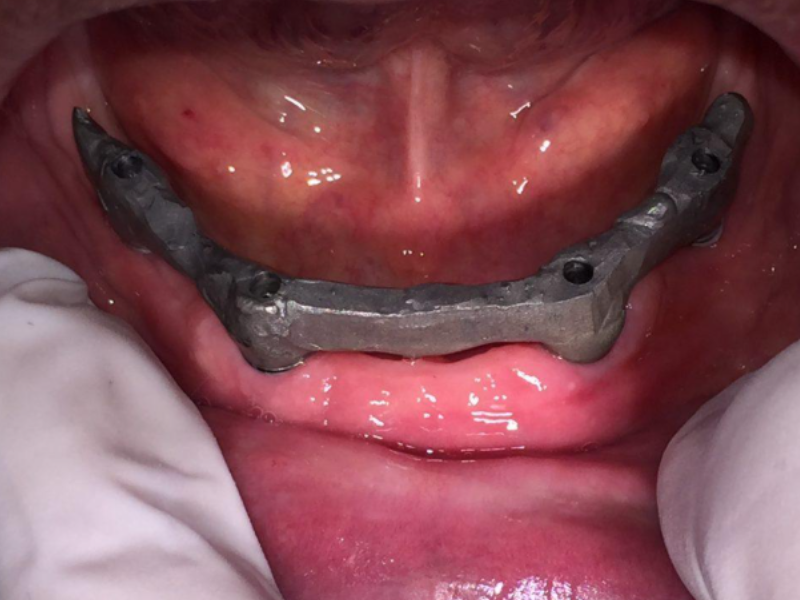

El sistema ALL ON FOUR consiste en la colocación quirúrgica de 4 implantes bien sea en el maxilar o en la mandíbula de manera estratégica y distribuidos biomecanicamente para soportar una estructura de barra, que llevará sobre ella una prótesis acrílica hibrida que se atornilla. Esta técnica es muy popular debido a que con tan solo 4 implantes podemos recuperar los 12 o 14 dientes de un maxilar de manera fija.

CASO CLINICO

Paciente edentulo total, portador de prótesis total acrílica convencional en estado funcional y con muy buena fijación en tejidos, desea tener sus dientes inferiores fijos.

Barra metálica